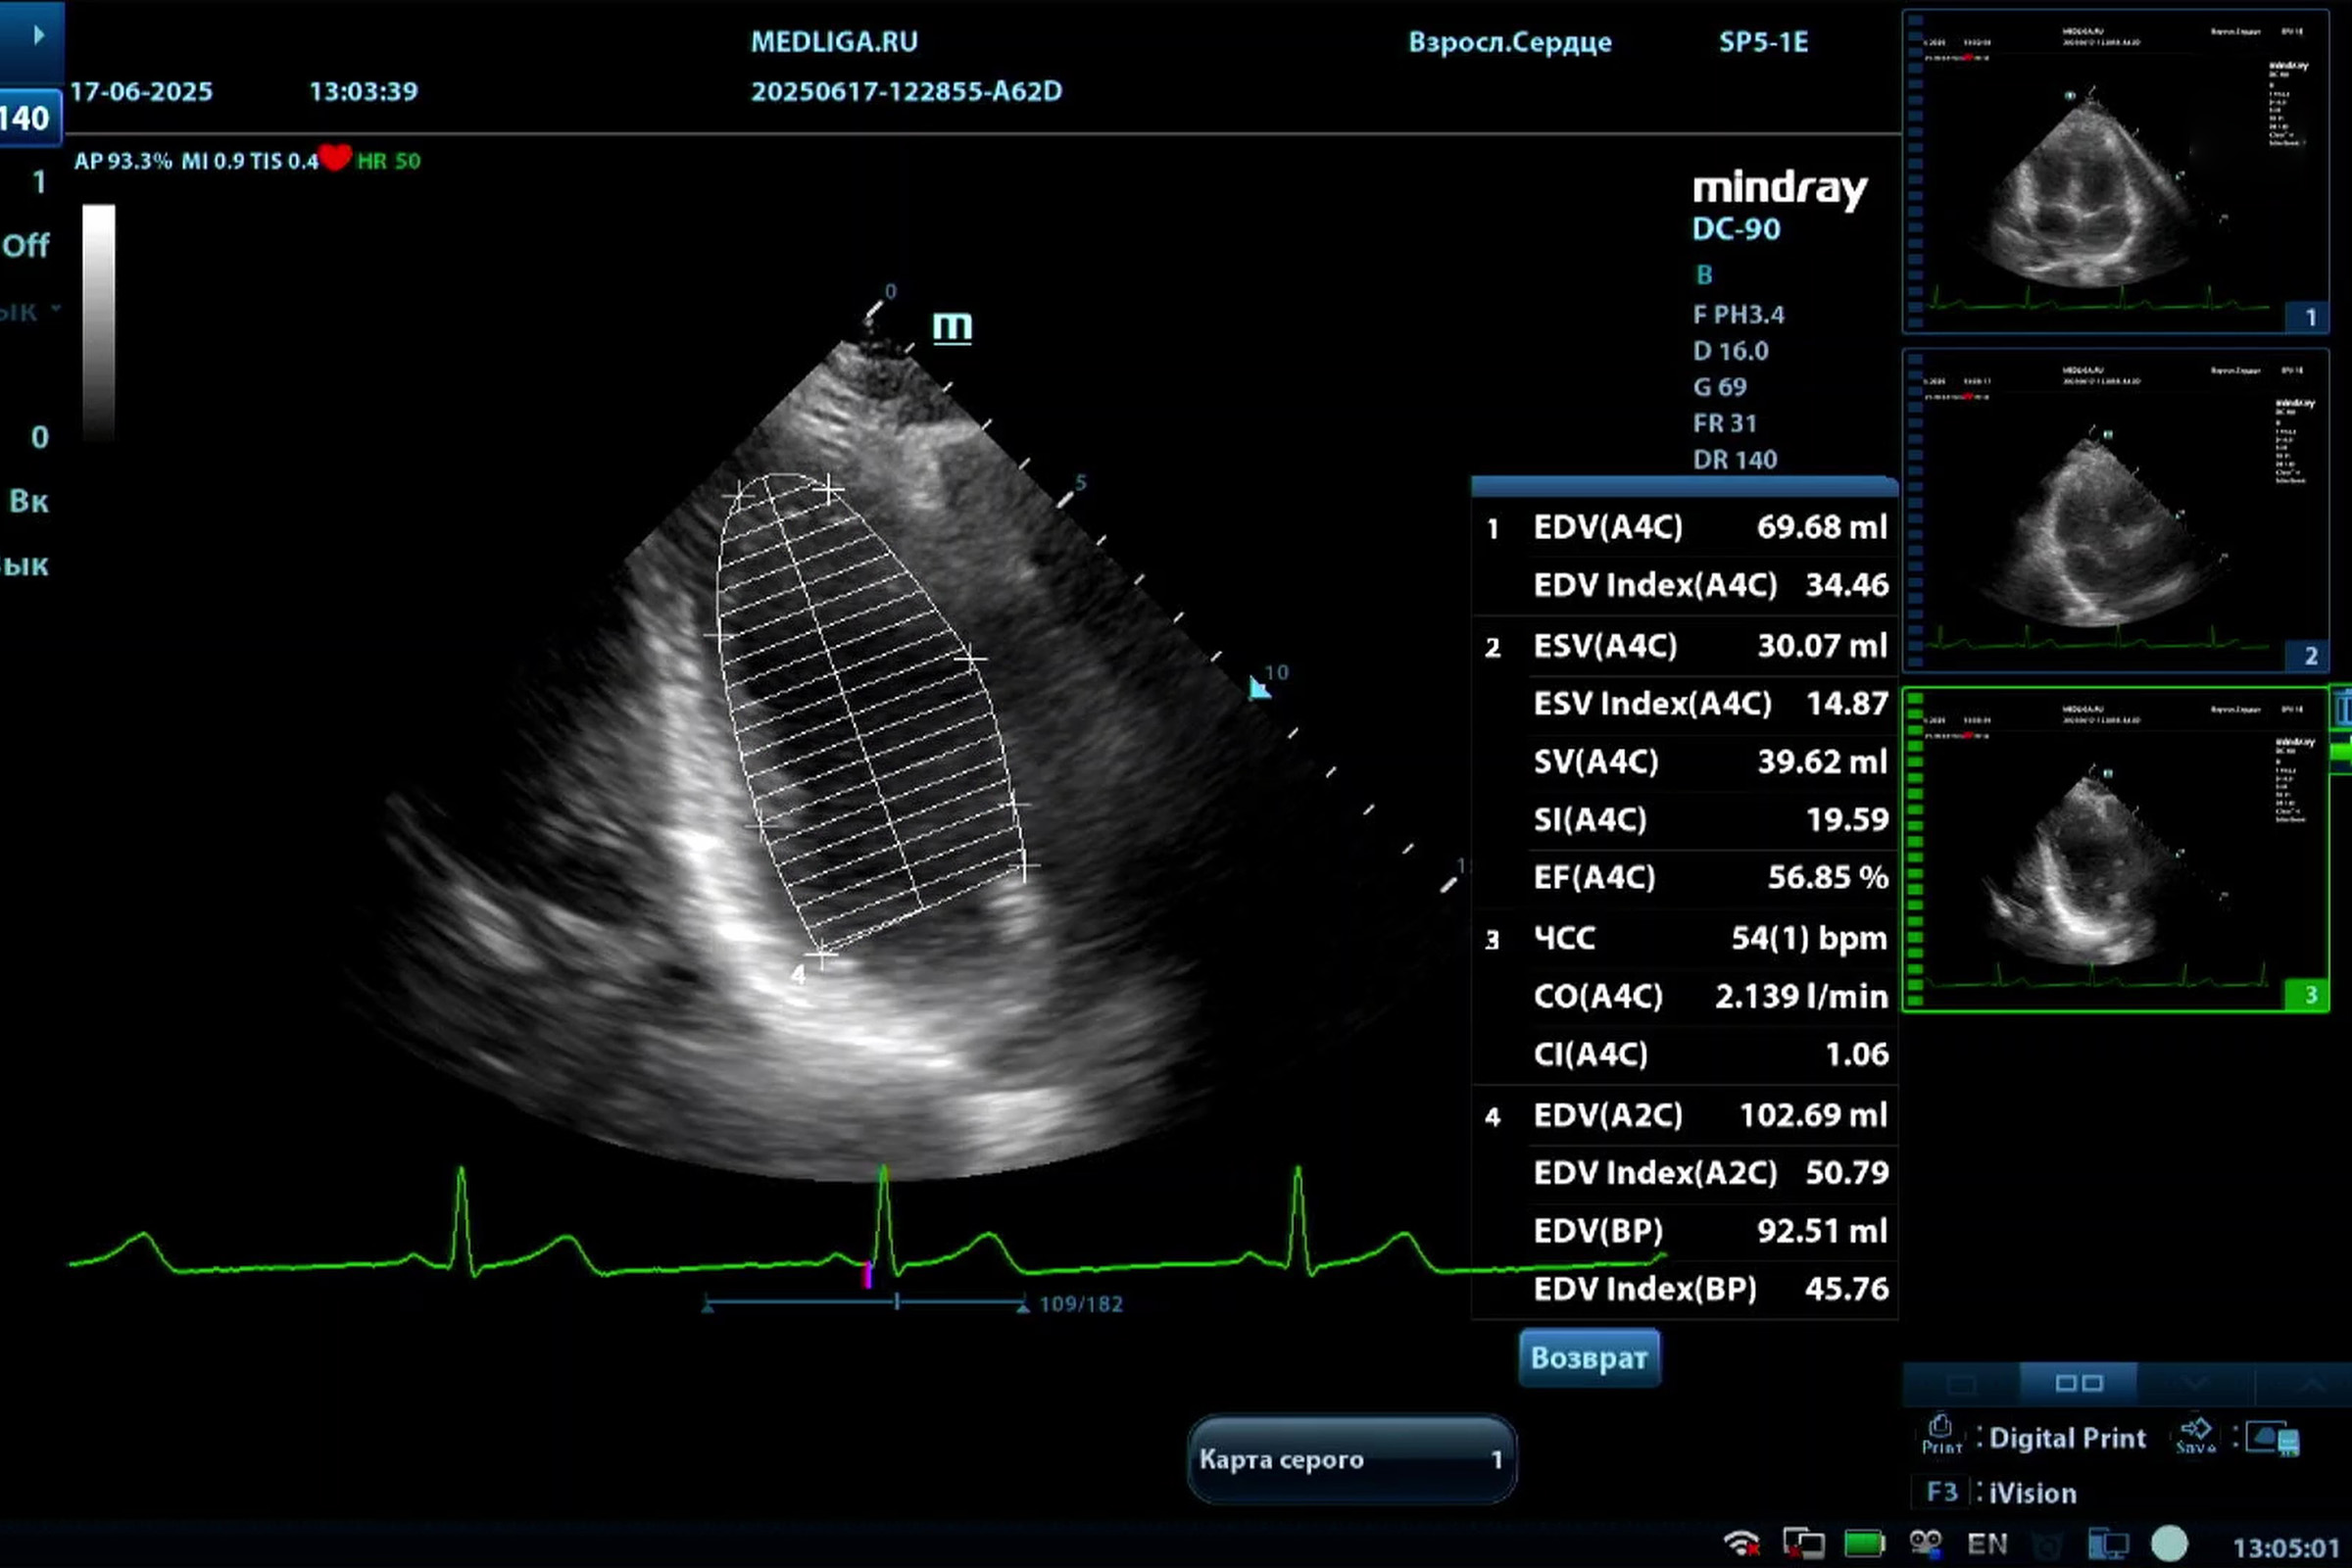

Медицинское оборудование для ультразвуковой диагностики